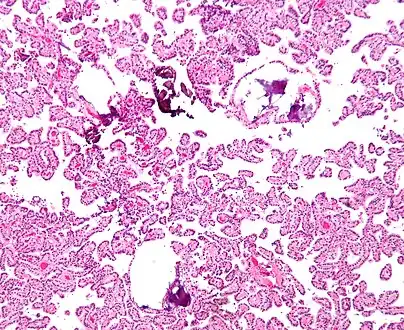

Micrograph of a choroid plexus papilloma. H&E stain.

Plexuspapillom Detail